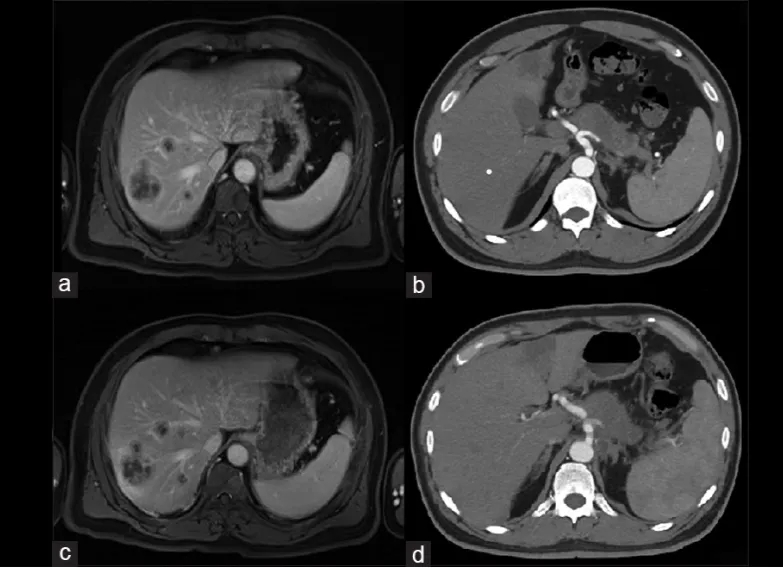

该患者为46岁男性,因上腹痛、CA19-9升高就诊,被确诊为胰腺导管腺癌(PDAC)伴肝转移(分期T4N1M1,IV期),胰腺肿瘤穿刺活检显示存在Robo1表达。治疗前CT及MRI扫描显示,胰腺存在约6cm×2.5cm×3cm的病变,伴淋巴结浸润,肝脏有多发性代谢亢进病灶(详见下图a、b),最大转移灶直径约3.5cm。因肿瘤无法手术切除且患者拒绝化疗,该患者入组接受Robo1特异性CAR-NK细胞输注治疗(临床试验编号:NCT03941457)。

治疗期间,患者在第2、3周静脉注射CAR-NK细胞后2小时出现中度发热(约38.5℃),24小时内迅速缓解;肝转移瘤穿刺注射后体温无明显变化。CAR-NK治疗后5个月内,胰腺病变及肝转移均得到控制(详见下图c、d)。后续未再给予进一步治疗,患者总生存期(OS)达8个月。

▲图源“JCRT”,版权归原作者所有,如无意中侵犯了知识产权,请联系我们删除